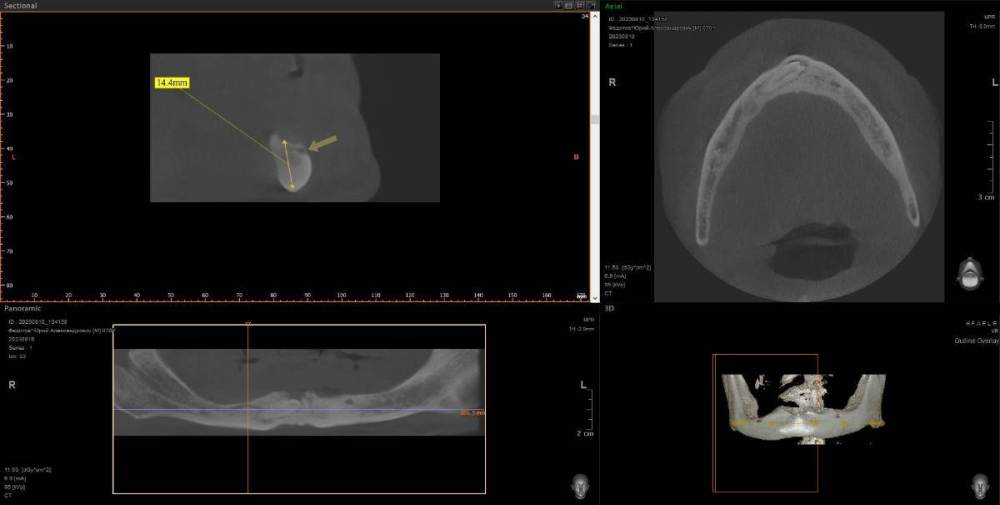

kriokov Опубликовано 10 августа, 2023 Поделиться Опубликовано 10 августа, 2023 ретенция клыка справа. кость 1 тип. Выход нерва почти по вершине. Сьемник не держится. М- 70 лет. Здоров. Нужен совет по установке имплантата справа под локатор, без удаления клыка. Слева штатно. Ссылка на комментарий

annda Опубликовано 13 августа, 2023 Поделиться Опубликовано 13 августа, 2023 (изменено) Предположу, что это должны быть как раз первые 4- 6 мм имплантата , корональная его часть( как при синус лифтинге том же) . в данном кейсе ( на втором соезе, что показан) совсем же другая ситуация. В этом ракурсе можно срез посмотреть не через коронку клыка, а через апикальную треть корня, над которым как раз и лежит массив своей губчатой кости.Посмотреть, сколько его там. А самый первый срез чем не устраивает ?Там область за местом выхода СНП или я не понимаю чего-то? Изменено 13 августа, 2023 пользователем annda Ссылка на комментарий

kriokov Опубликовано 13 августа, 2023 Автор Поделиться Опубликовано 13 августа, 2023 10 часов назад, annda сказал: А самый первый срез чем не устраивает ?Там область за местом выхода СНП или я не понимаю чего-то? Думаю првильно понимаете, это более менее позиция, 6 часов назад, TIGER сказал: 2 импланта под 30 гр м.ю,балочка между ними,и никакого гемора с клыком и локаторами как вариант, да + Ссылка на комментарий